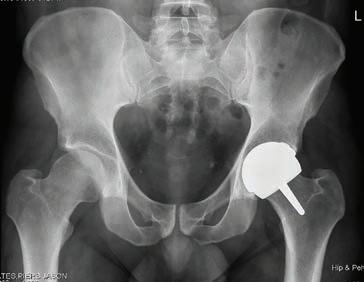

Getting hip about early care

Every year, more than 19,000 Australians – many of them elderly –fracture their hip. Now revised guidelines are aimed at ensuring they get more timely treatment.

WA geriatrician Dr Hannah Seymour knows only too well that time can be the enemy when treating people who break their hip, particularly when facing geographical barriers.

Based at Fiona Stanley Hospital, her experience of working closely with older patients who have had a hip fracture means Dr Seymour understands that prompt surgery reduces pain, speeds recovery and reduces time spent in hospital.

Yet as hip fracture surgery can only be performed at larger hospitals with suitable facilities, some people in regional and remote areas have to be transferred long distances. In 2022, 14% of hip fracture patients in Australia were transferred from another hospital for their surgery.

However, updated guides for the care of hip fractures are now calling for hospitals to move more quickly to get patients into theatre – and up walking after their surgery.

The Australian Commission on Safety and Quality in Health Care (ACSQHC) launched a revised national clinical care standard for hip fracture in September at the binational Hip Fest 2023 conference, hosted by the Australian and New Zealand Hip Fracture Registry.

Cut the wait

The standard was first launched in September 2016 to guide consumers, clinicians and health services on delivering appropriate care to people with a hip fracture. The revised standard reduces the recommended maximum time to surgery, along with other improvements for better care.

The commission said many people with a hip fracture were waiting longer than was optimal for surgery, despite some hospitals making big improvements in the past few years.

Australia’s ageing population made improvements to hip fracture care even more important, as most fractures occur in people aged over 65 who are more vulnerable to complications.

Hip fracture significantly increases an older person’s risk of death, with one in four people dying within 12 months. Of those who survive,

many lose their ability to live independently or return to their former lifestyle.

The updated standard for hospitals has reduced the maximum time to surgery from 48 hours to 36 hours, in line with international guidelines. For the first time, this explicitly includes patients who need to be transferred to a hospital that can perform the surgery.